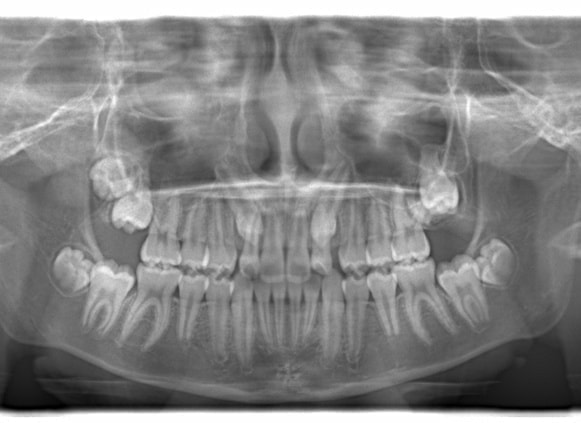

FX(フェイシャルアキシス)は85度なので東洋人の平均値に近く、下顎が前方に過剰成長するリスクは強くはありません。

しかしやはり上顎は劣成長で、下顎が優位な状態ではあります。

上下顎のギャップはありますが、顔面自体の幅径は良好な値を示していますので、スペース不足は拡大することによって解決できポテンシャルはあると考えられます。

左右の非対称もさほど強くありません。

骨年齢は実年齢よりも低めなので、今後下顎の旺盛な成長が見込まれます。

検査時のレントゲン分析では、上下顎の関係は、上顎の劣成長があり下顎前突傾向という値がでておりましたが、前歯ジャンプ後はフェイスマスクの効果もあり、上下顎の関係は正常化しています。